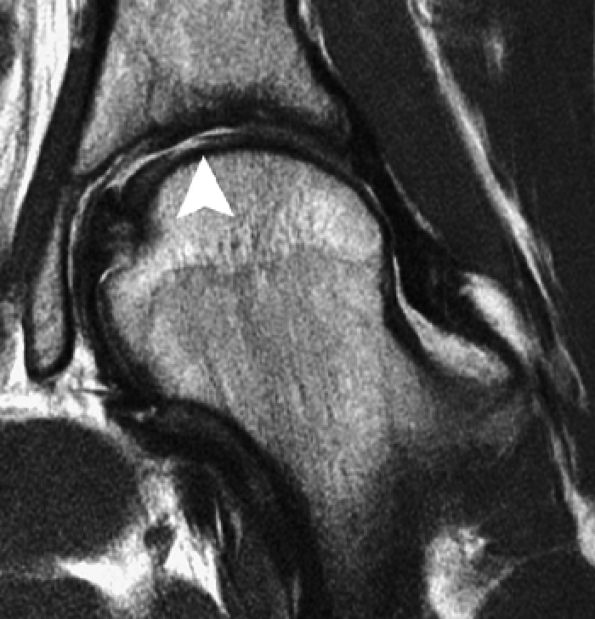

![]() |

FIGURE 7.17 ● Axial (A) and sagittal (B) fast spin-echo MR images of the knee in a 15-year-old boy following a patellar dislocation demonstrate an osteochondral fracture of the medial facet (arrows). The displaced osteochondral fragment is seen against the synovial reflection of the ACL (arrowhead). Note the presence of high-signal-intensity bone marrow, low-signal-intensity subchondral plate, and intermediate-signal-intensity cartilage in the displaced fragment, distinguishing it from an isolated chondral shear.